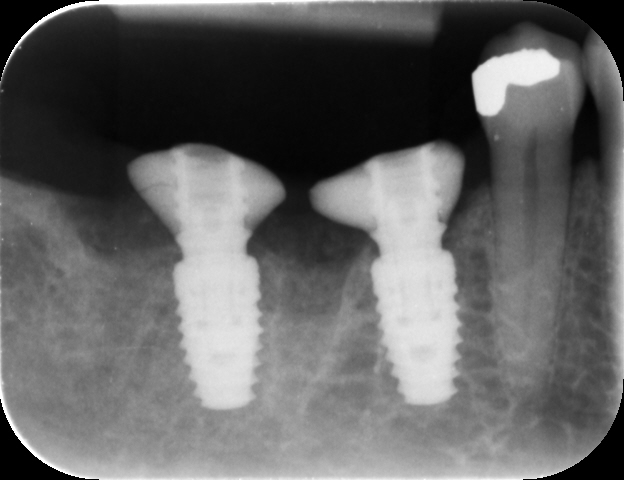

Dental implants were then placed using the sleeveless surgical guides. The guided kit from CONELOG® is fantastic, as the screw-in carriers allow for very accurate positioning. After verifying the implant placement, the carriers are replaced and can be used to maintain patency of the implant opening while the graft material is packed into the site.

For this case, 5.0 mm x 9.0 mm CONELOG® Progressive-Line implants were utilised, which is a highly favourable system for immediate placement. The design features that make it particularly effective include:

• Aggressive thread design for high primary stability.

• Promote® (sand blasted, acid etched) surface treatment, promoting rapid osseointegration.

• Grade 4 titanium, commercially pure titanium offering predictable integration.

CONELOG® Progressive-Line implants are especially well-suited for molar sites due to the conical connection with platform switching. When combined with the correct depth of placement, this ensures stable crestal bone levels over time. One of the standout features is the availability of varying sizes, including a 5mm implant that allows for a conical connection while maintaining a less aggressive emergence profile compared to other systems.